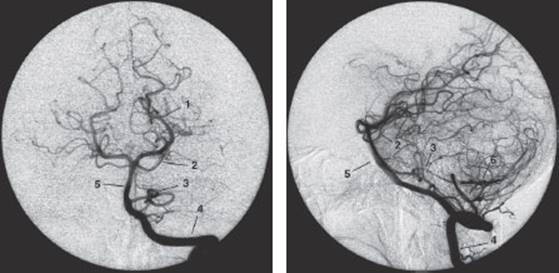

Methods. Conventional arteriography, also known as angiography with radiological contrast media, is indicated for certain special purposes, e. g., the preoperative visualization of intracranial aneurysms or arteriovenous malformations. This type of study involves the introduction of an intra-arterial catheter by way of the femoral a. along a guide wire all the way up to the great vessels supplying the brain. Contrast medium is injected into these vessels while fluoroscopic images are simultaneously obtained. The image changes from one second to the next, as the contrast medium distributes itself in the vascular system of the brain. All of the images are digitized and an image obtained before any contrast medium was injected is subtracted from each to generate a digital subtraction angiogram, which shows nothing but the blood vessels supplying the head and brain (both extra- and intracranial). Contrast medium can be injected into the carotid a. to display the anterior circulation (Fig. 4.8), or into the vertebral a. to display the posterior circulation (Fig. 4.9).

Fig. 4.9 Selective angiography of the left vertebral a. a Arterial phase, anteroposterior projection, b Arterial phase, lateral projection.

1 posterior cerebral a.

2 superior cerebellar a.

3 anterior inferior cerebellar a. (AICA)

4 left vertebral a.

5 basilar a.

6 posterior inferior cerebellar a. (PICA)